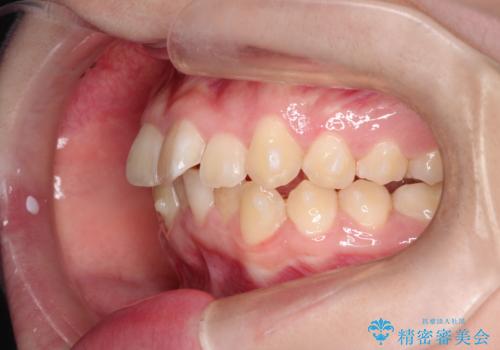

なるべく通院回数を減らして矯正したい インビザラインでのガタガタ矯正

- 上下の歯並びを治したいとのことで来院されました。

受験生ということもあり、なるべく通院回数を減らしての矯正を希望されたので、インビザラインで治療をすることにしました。